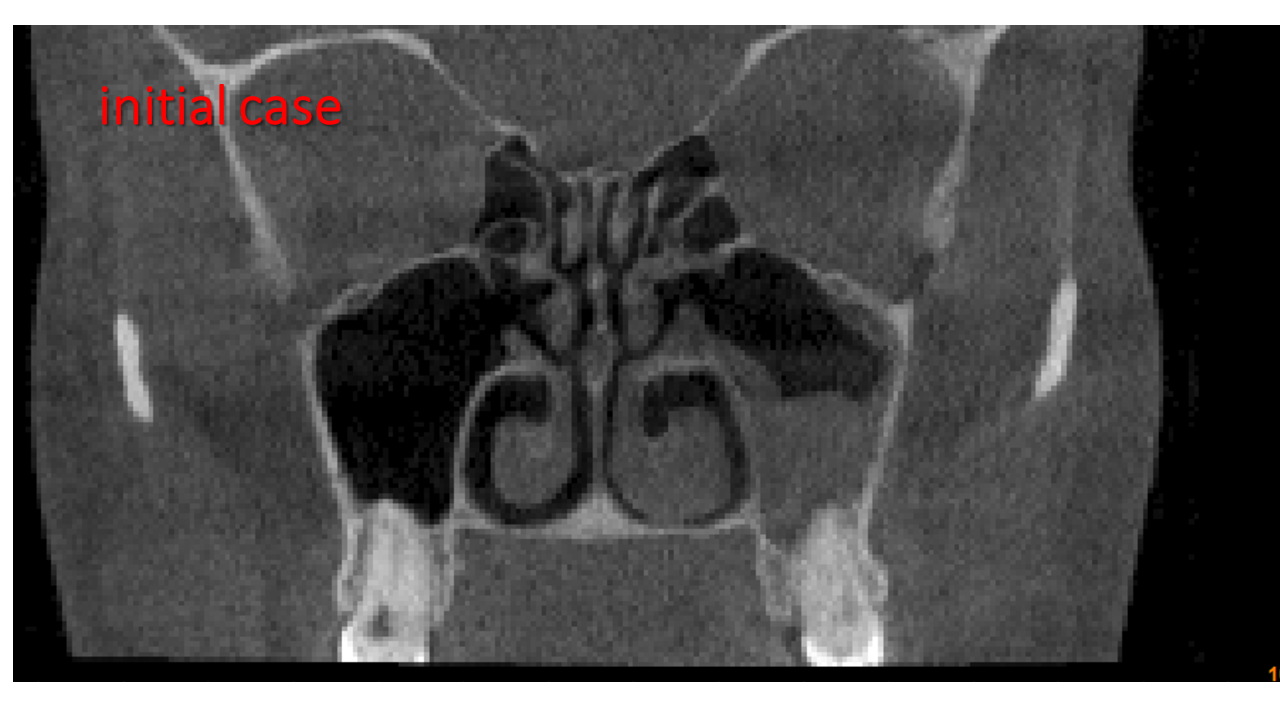

FESS Case Review and Radiologic Analysis (30.09.2016)

Case-based presentation focused on pre- and postoperative imaging in functional endoscopic sinus surgery (FESS). Includes anatomical landmarks, surgical variations, sinus pathology, and technique evaluation. Delivered by Dr. Levon Galstyan at AAOMFS.